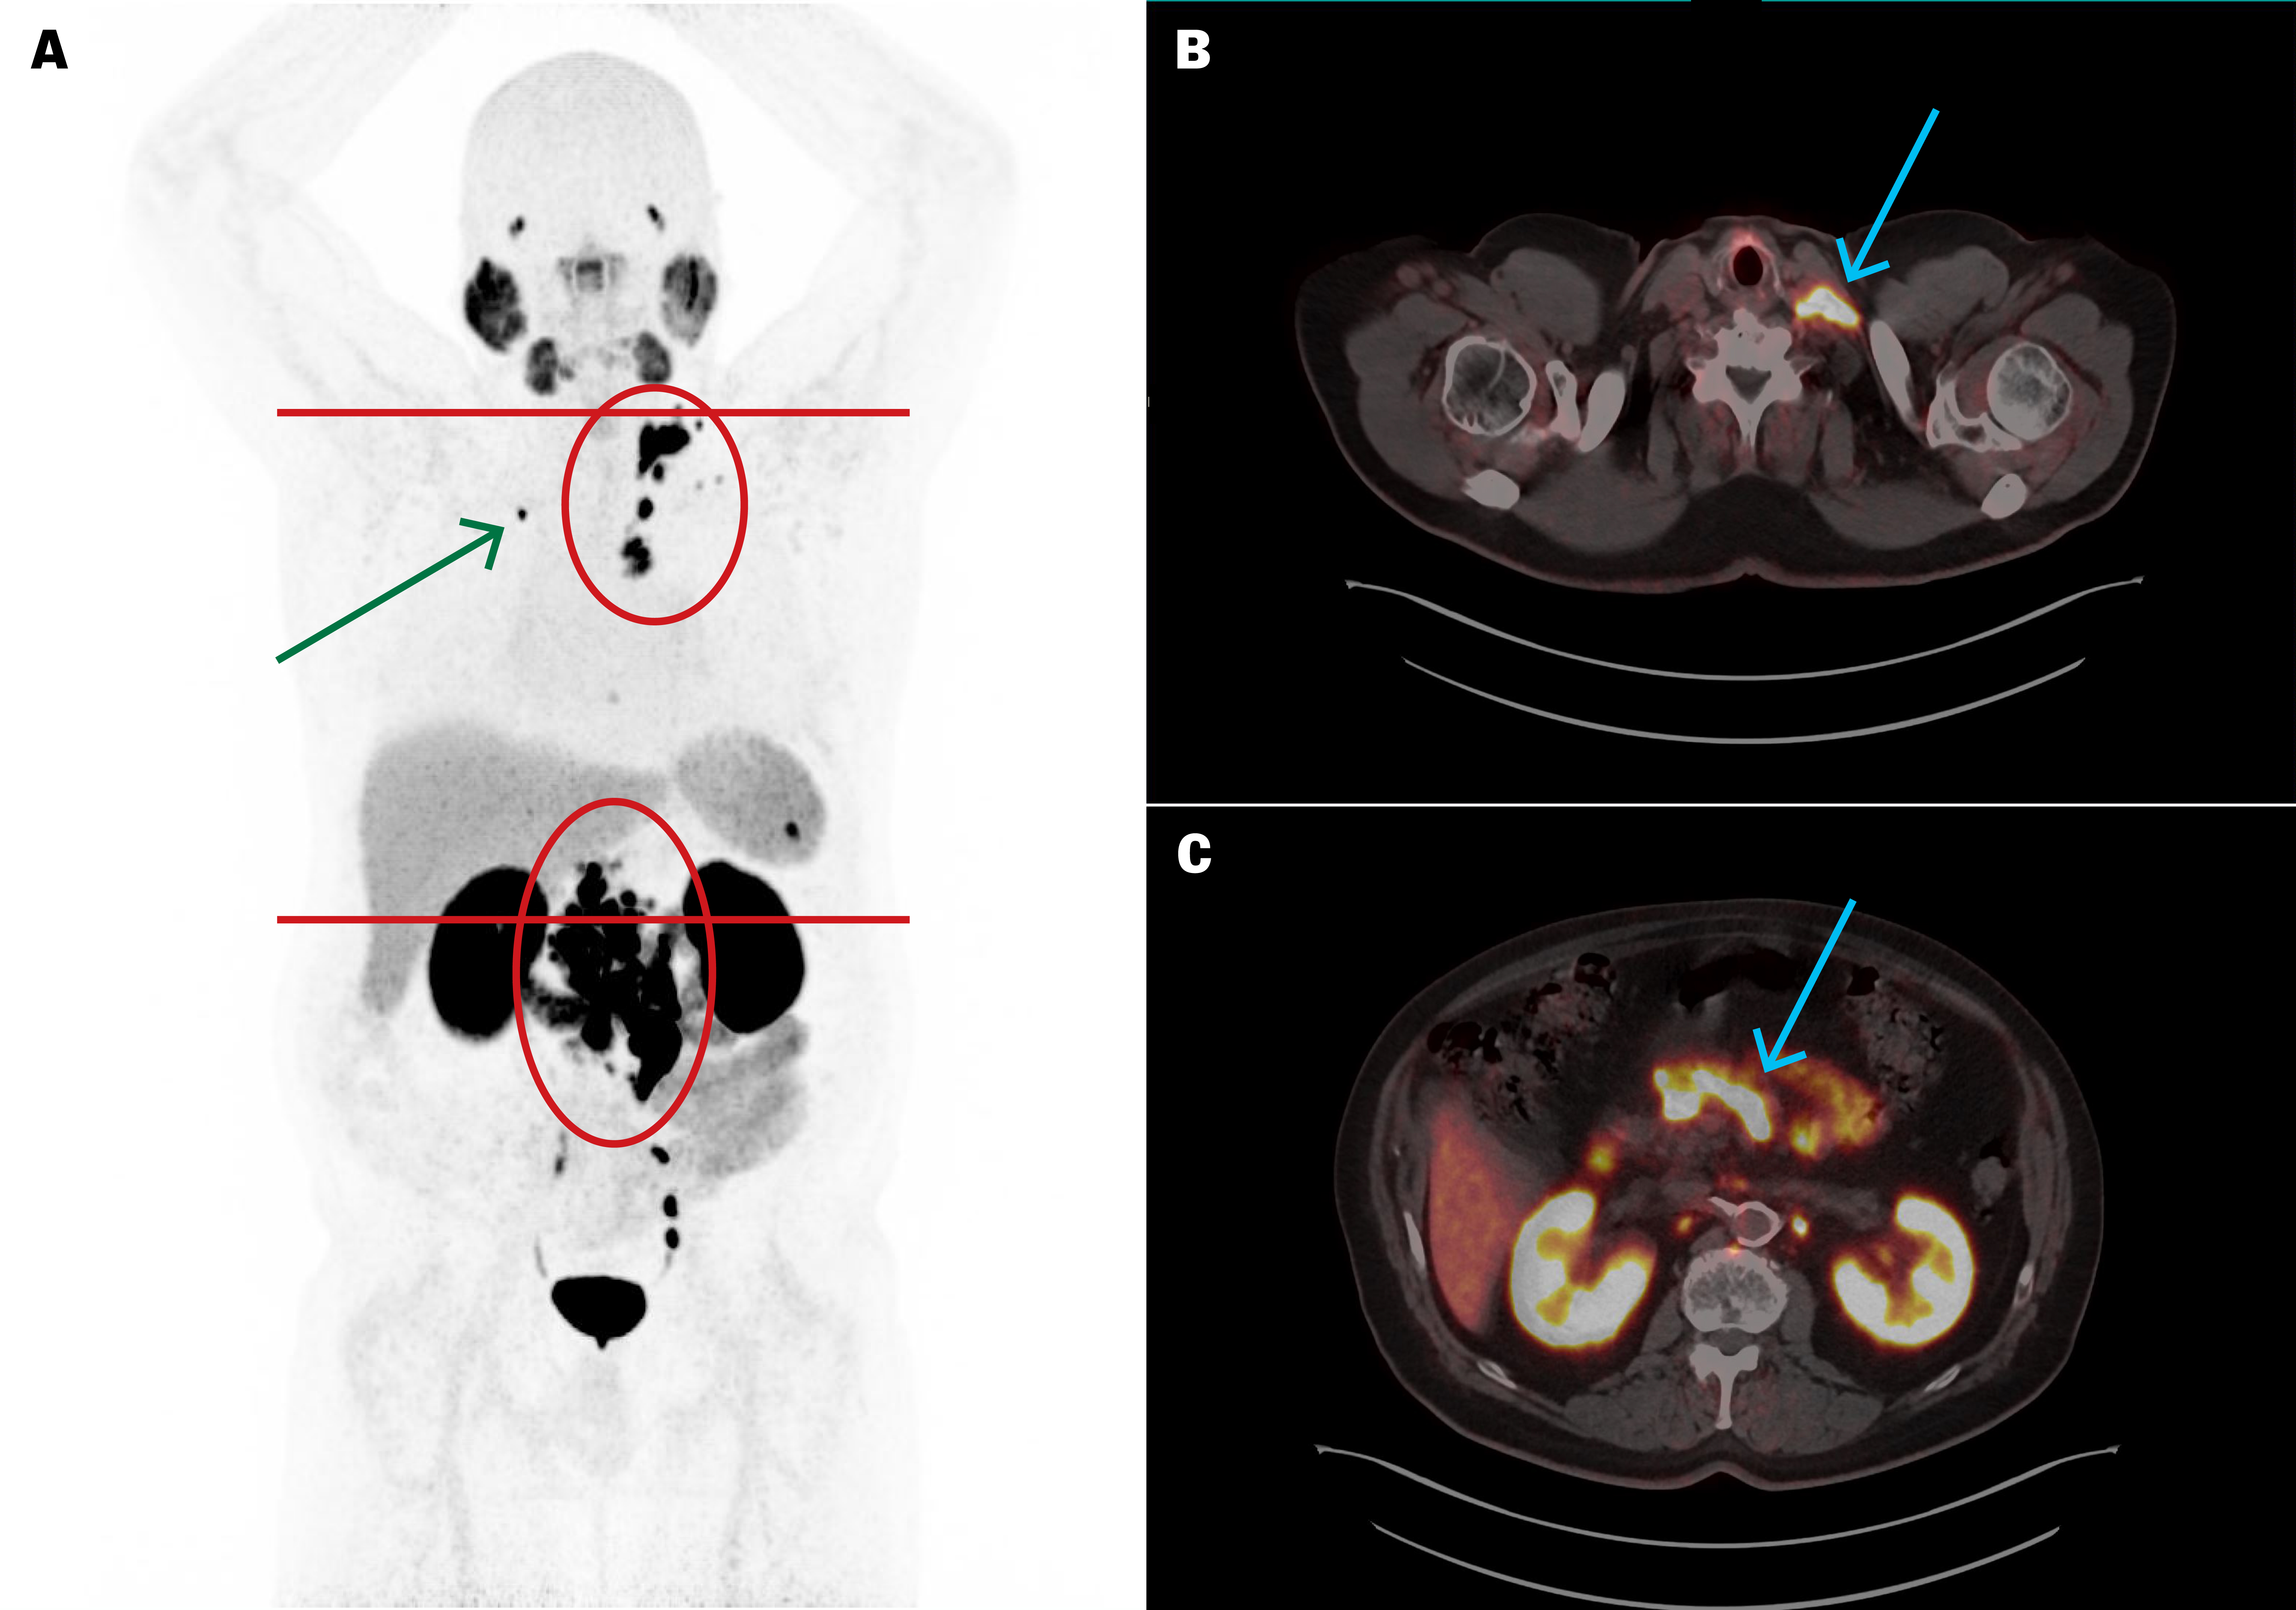

PSA i plasma (p-PSA, referanseområde 0–4,0 µg/L for menn ≥ 60 år) var 154 µg/L og PSA-doblingstiden var 4,5 måneder. PET/CT med det radiofarmasøytiske sporstoffet prostataspesifikt membranantigen radioligand (PSMA-RL) merket med Gallium-68 ([⁶⁸Ga]PSMA-11) viste meget høyt opptak i utbredte metastatiske lymfeknuter i bekken, abdomen, toraks og hals, samt en solitær skjelettmetastase i høyre krageben (figur 1). Opptaket indikerte at det kunne ligge til rette for behandling med PSMA-ligand merket med den beta-emitterende radionukliden Lutetium-177 ([¹⁷⁷Lu]PSMA-RL).